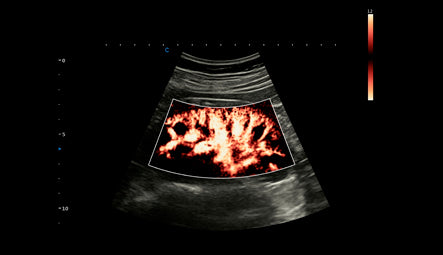

Evaluación Vascular con SonoPW

La funcionalidad de Doppler pulsátil (SonoPW) del SonoMax 9 permite la evaluación precisa de la velocidad del flujo sanguíneo, lo cual es crucial para la valoración de la dinámica vascular en diversas condiciones clínicas. Esta herramienta proporciona datos detallados sobre la hemodinámica, esenciales para el diagnóstico y seguimiento de enfermedades cardiovasculares. La precisión y fiabilidad del SonoPW ayudan a los médicos a evaluar con exactitud el estado de los vasos sanguíneos y la función cardíaca.